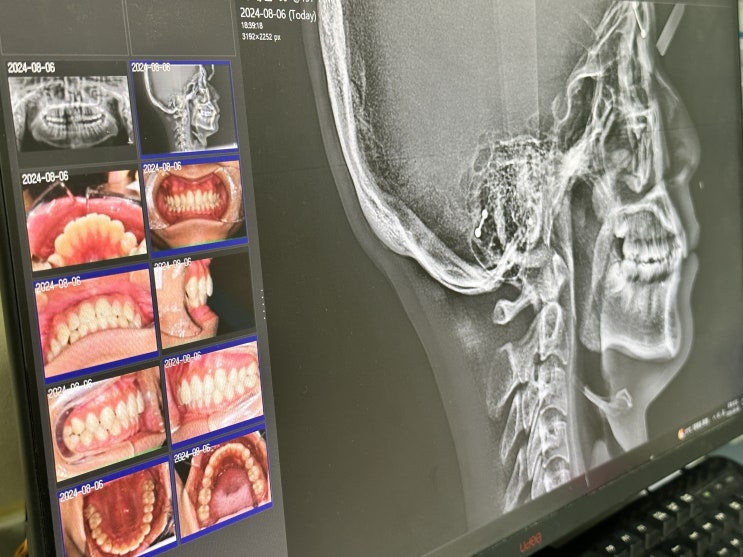

아산 치아교정 치과를 찾고 계시다면!!! 교정과 전문의가 있는

안녕하세요, 아산 시민 여러분! 365아홉가지약속치과 탕정점 입니다. 오늘은 많은 분들이 관심 갖고 계신 ...